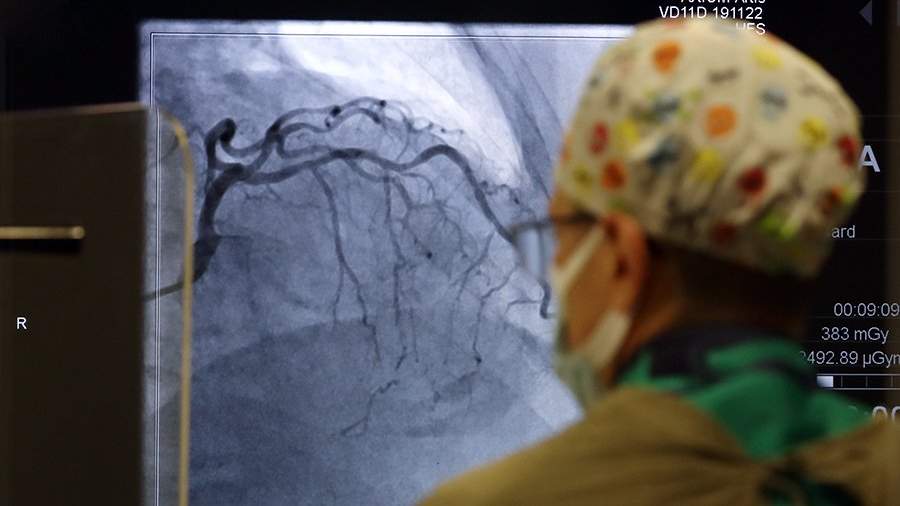

Врач Лакша: ультразвуковое исследование артерий шеи поможет выявить риск инфаркта и инсульта

Врач Евгений Лакша в интервью «Газете.Ru» рассказал об исследовании, благодаря которому можно определить риск инфаркта и инсульта.

Речь идет об ультразвуковом исследовании артерий шеи, показывающем изменения, которые в будущем могут обернуться болезнью, сказал доктор в понедельник, 18 июля.

«Смысл исследования заключается в поиске атеросклеротических бляшек, вызывающих сужение артерий, что со временем может вызвать ишемию и стать причиной инсульта или инфаркта. УЗИ также позволяет оценить структуру бляшки и вероятность ее осложнения (изъязвления или фрагментации). Это грозит формированием тромбов, способных перекрыть просветы артерий», — пояснил он.

Лакша подчеркнул также, что инсульт головного мозга и инфаркт миокарда на сегодняшний день являются одними из самых частых причин гибели людей.

«Причем это наблюдается не только у возрастных людей, но и в более молодом возрасте. Причин развития этих недугов много, однако часто на первых порах важнее оказывается не поиск источников, а выявление предрасположенности к этим угрожающим жизни состояниям», — заверил он.

Как отметил специалист, атеросклероз редко бывает изолированным, по этой причине обнаружение бляшек в артериях шеи является маркером для поиска их в других частях организма, к примеру, в артериях, которые питают сердце. Это сможет предотвратить угрозу жизни на ранних сроках.